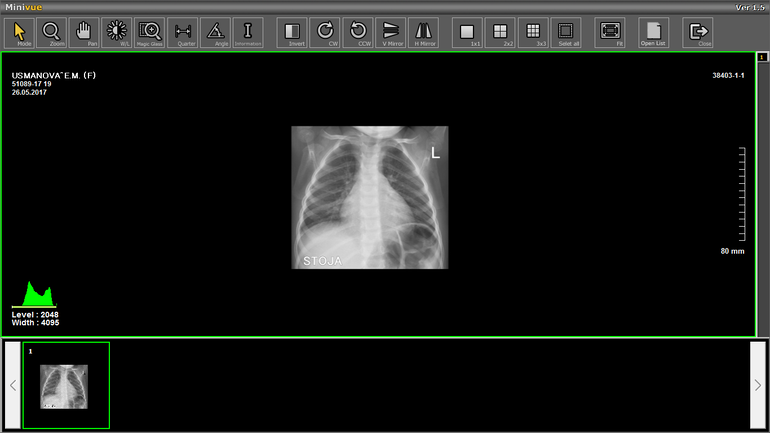

Снимки от 26 мая и 31 мая

С 28 апреля был бронхит. 12 мая поставили пневмонию, уколы и т. д. динамика была все хуже, скопилась жидкость в легких. Легли 22 мая в Морозовскую больницу, жидкость ушла при лечении. И врач сказал что есть положительная динамика по снимкам, отдали на руки диски и выписали. Я дома открыла и не пойму что дальше делать. Дочь опять стала кашлять сильно, отхаркивая, температура 37,5 держится постоянно. Нам назначили просто пить Амбробене. Сказали что после пневмонии температура это нормально. Неужели лечение завершено? Кровь завтра идем сдавать по месту жительства. Антибиотики Цифипим в капельницах и Суммамед 5 дней в больнице были. Есть у нас тут детские доктора, помогите, направьте пожалуйста.